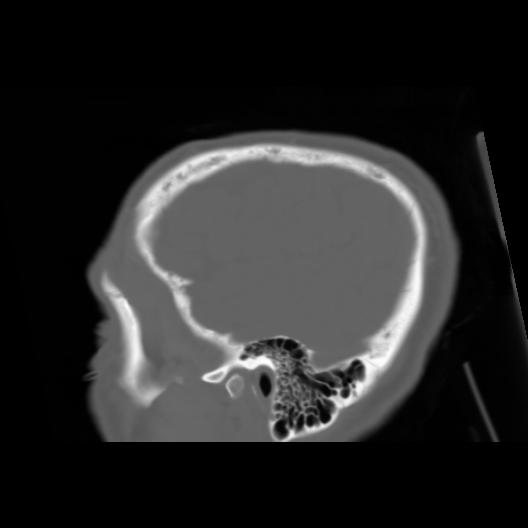

6 CEREBRO,,Sagittal,3.000,CEREBRO,Sagittal,